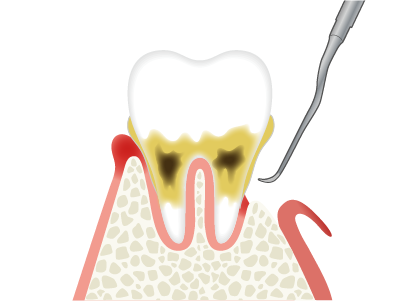

SRPでも改善が見られない重度の症例では、歯肉を切開してポケット奥深くまで歯石などを除去する外科的処置を行います。

歯周病菌の炎症が歯茎の内側にも進行、歯を支える骨(歯槽骨)にも影響が出始めている段階。腫れ・出血・冷たいものがしみるなどの症状が出ることがあります。

歯槽骨の1/3〜1/2が破壊された状態。歯茎の腫れ・出血・膿・歯のぐらつき・口臭など自覚症状がかなり出ます。

歯槽骨の2/3以上が溶け、歯根が露出し、歯茎からの出血・膿・口臭・歯のグラつきがひどくなり、食事ができないほどになる事もあります。このまま放置すると自然に歯が抜け落ちる可能性があります。